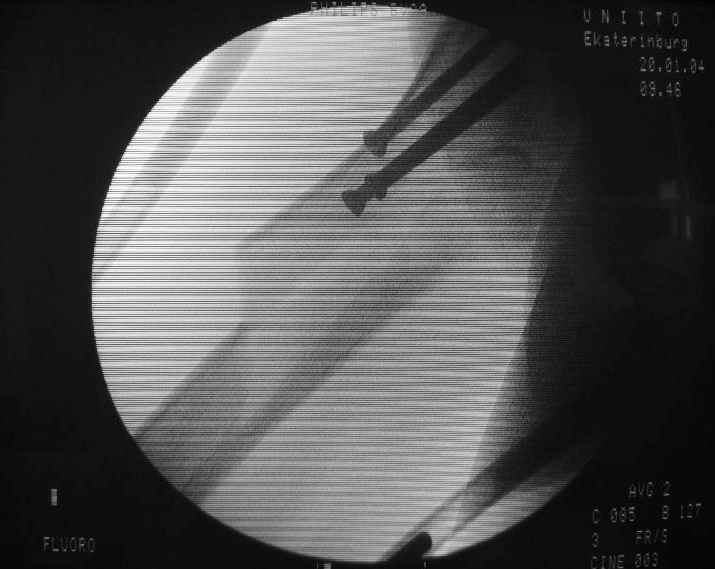

Отправитель: Alexander Chelnokov 20 Январь 2004, 19:24

Еще одна боковая проекция. На сегодня назначен закрытый интрамедуллярный остеосинтез. Реконструкционного гвоздя для этой больной не нашлось, придется делать обычным.

Another lateral view. A closed nailing is scheduled for today. No reconstuction nail is available so a usual one is planned.